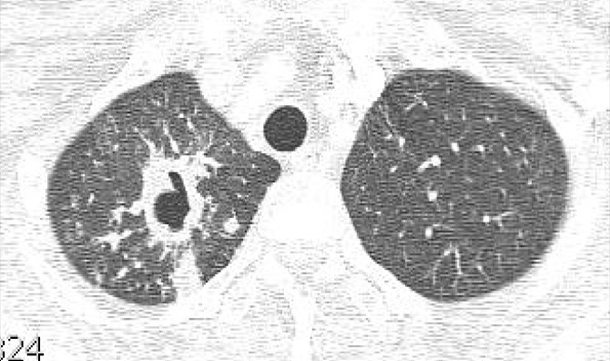

환자의 임상 증상 문진과 진찰 후, 흉부 X선 검사 및 흉부 CT가 진단에 도움이 됩니다.

• 폐결핵 비결핵성항상균 폐질환

img img

그림: 폐결핵과 비결핵성항산균 폐질환의 흉부엑스레이 사진과 흉부전산화단층활영 사진

비결핵성항산균 폐질환은 폐결핵과 비교하였을 때 서서히 진행하거나 변하지 않을 수 있으며, 만성적인 경과를 보이고, 진단이 늦어지는 경향이 있습니다. 두 질환은 모두 환자의 객담을 통한 객담 항산균 도말검사, 객담 항산균 배양 검사를 진행합니다. 객담 배양이 되기 전에는 객담 도말 검사 양성 소견만으로는 결핵균과 비결핵성항산균이 구별이 되지 않으며, 구별을 위해서 결핵균 핵산증폭검사(TB-PCR) 검사를 시행합니다.

비결핵성항산균 폐질환의 경우는 진단 자체가 치료를 의미하지 않으며, 흉부 X선이나 흉부 CT상에서 공동이 되는 등 병변이 심하고, 증상이 심한 경우에는 동정된 균주에 근거하여 항생제 치료를 시작할 수 있습니다.